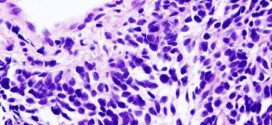

Leer MásCÁNCER ESCAMOSO DE LAS VÍAS AERODIGESTIVAS SUPERIORES (CE-VADS)

El cáncer escamoso de las vías aerodigestivas superiores (CE-VADS). Las vías aerodigestivas superiores (CE-VADS), están formadas por la cavidad nasal, la boca, la faringe y la laringe; a ese nivel se conforma una encrucijada entre la vía aérea y la vía digestiva. Durante los primeros años de vida de una persona, las células normales se dividen más rápidamente para permitir …